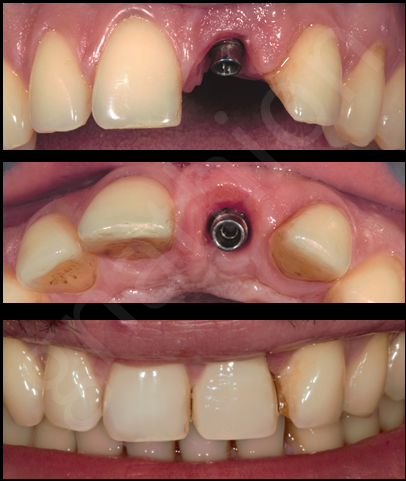

Μετά απο 5 μήνες έγινε «αποκάλυψη» του εμφυτεύματος και κατασκευάστηκε προσωρινή στεφάνη η οποία παρέμεινε κοχλιωμένη για 3 ακόμη μήνες έτσι ώστε να προσαρμοστούν πιο αρμονικά και αισθητικά οι μαλακοί ιστοί της περιοχής στην προσθετική υπερκατασκευή του εμφυτεύματος(Εικόνες 3 και 4).

Η τελική κοχλιούμενη αποκατάσταση απεικονίζεται στην εικόνα 5 και μια σύγκριση με την αρχική κατάσταση στην εικόνα 6.